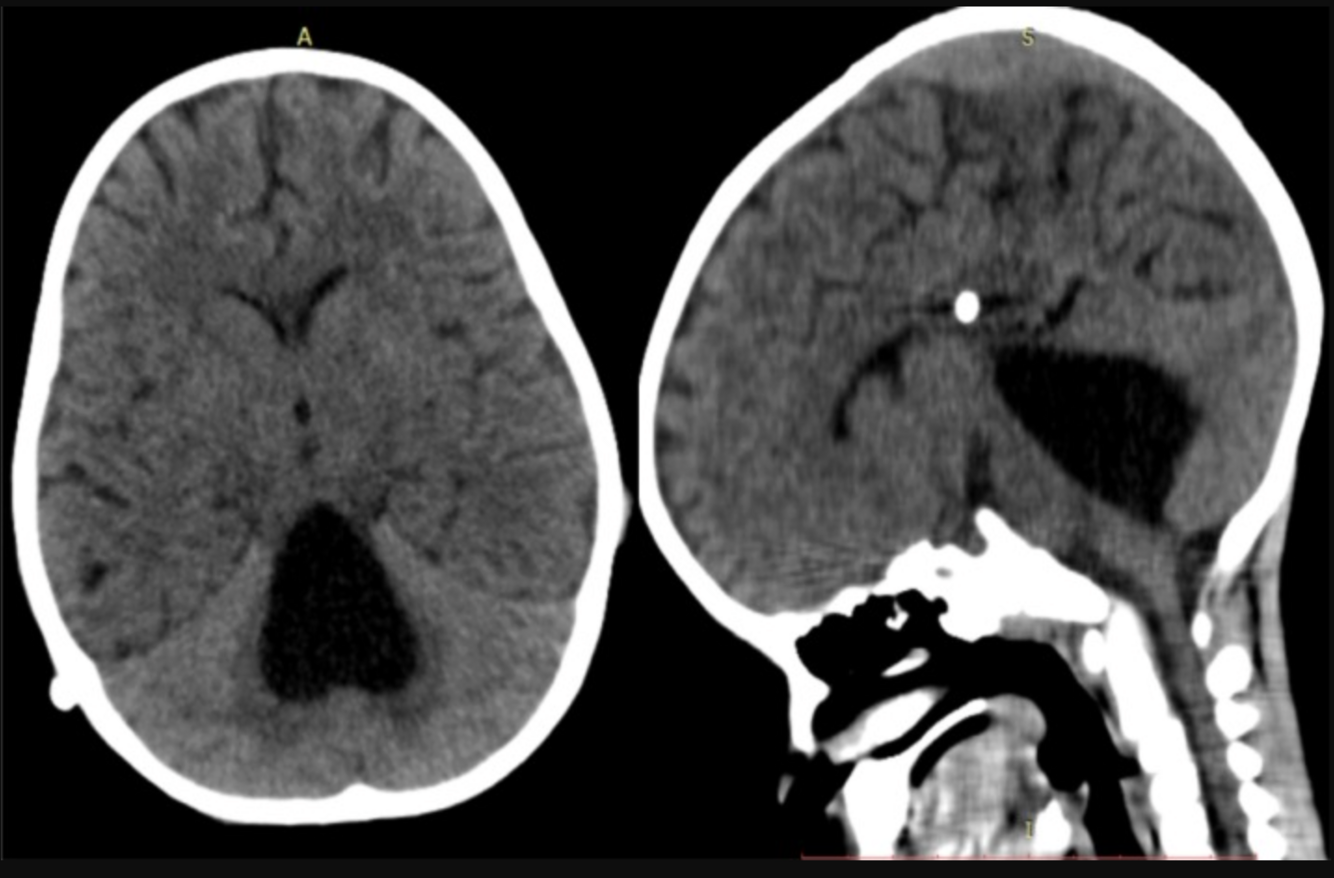

Remarks on CT scan results in patients with suspected shunt malfunction

**Compare with previous CT scans because many patients with shunts have an abnormal baseline ventricular size.** **Unremarkable findings on CT and/or radiographic shunt series cannot be relied on to exclude shunt obstruction**ª **Thus, obtain neurosurgical consultation whenever shunt malfunction is suspected** ## Footnote ª*Between 9% and 15% of pediatric patients will have profound alterations in brain compliance leaving ventricular size unchanged even in profound shunt failure with high intracranial pressures.*